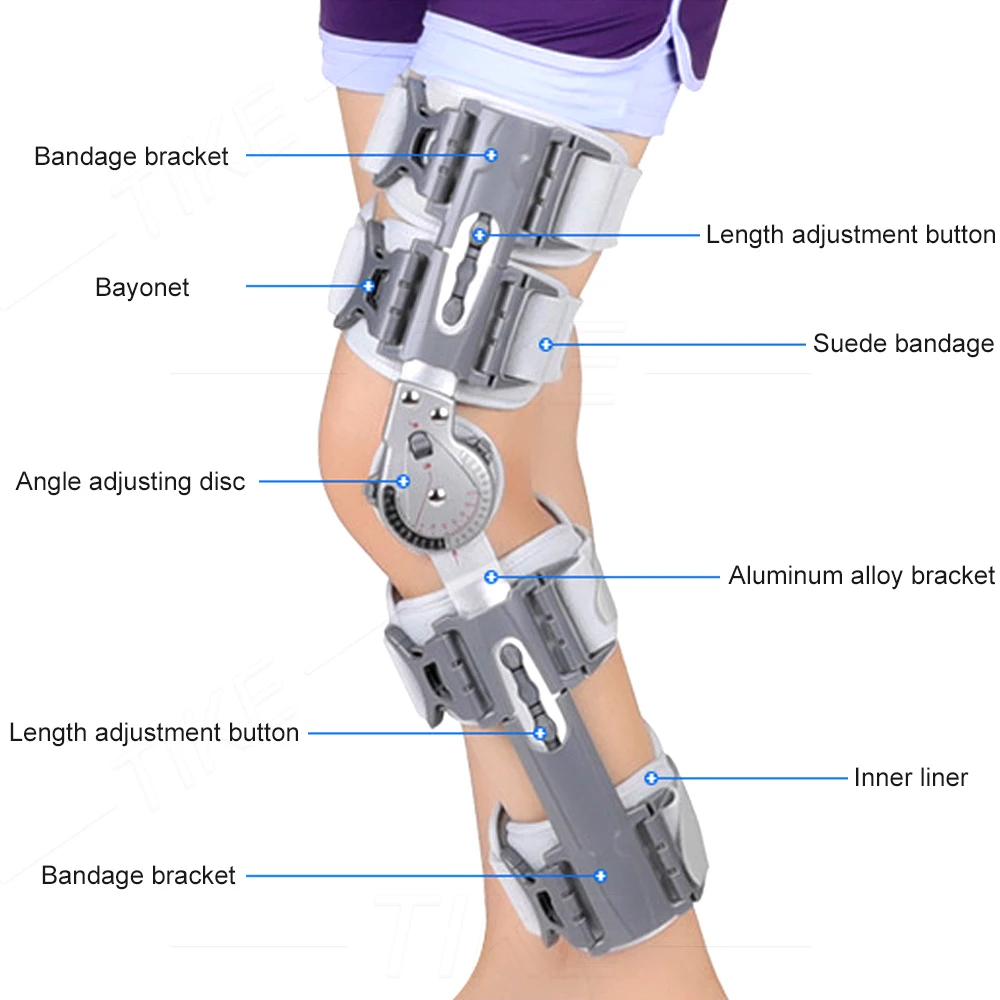

Tike Rom Csuklós Térdtartó Immobilizáló Ortózis Stabilizátor Acl Mcl Pcl Sérüléshez, Az Ortopédiai Rehabilitációs Poszt Helyreállítási Támogatása

Darabszám: Egy egység

Alkalmazás: Láb

Hatás: Bone Care

Anyaga: kompozit anyag

Modellszám: csuklós térdmerevítő

Elem típusa: merevítők és támasztékok

Szín: ezüst

Alkalmazható személyek: Felnőtt férfiak, nők

térdtámasz: műtét utáni térdmerevítő

lábmerevítő: acl sérülés térdmerevítő

acl merevítő: acl műtét utáni merevítő

térdmerevítő: post op térdmerevítő

térdstabilizátor: teljes hosszúságú csuklós térdmerevítő

térdmerevítő: térdmerevítő mcl sérülés

térdeszköz: molett térdmerevítő

csuklós merevítő: post op acl térdmerevítő

térdmerevítő: reteszelő csuklós térdmerevítő

acl csuklós merevítő: nagy csuklós térdmerevítő

csuklós térdmerevítő: térdmerevítő zárral

acl merevítő térd: térdmerevítő acl műtét

térdmerevítő műtét: csuklós acl térdmerevítő

stabilizáló térdmerevítő: mcl térdmerevítő csuklós

lábstabilizáló merevítő: csuklós térdtámasztó merevítő

zárt térdmerevítő: csuklós jobb oldali térdmerevítő

stabilizátor térdmerevítő: mcl térdmerevítő csuklós stabilizátor

mcl brace térd: orvosi térdmerevítő zsanérral

acl javító merevítő: meniszkusz térdmerevítő műtét után

pcl térdmerevítő: csuklós térdmerevítő stabilizátor

sípcsont térdmerevítő: állítható zárható térdmerevítő

térdtámasz: állítható, rögzítő térdmerevítő

teljes lábmerevítő: a legjobb térdmerevítő műtét után

hibged térdmerevítő: post op csuklós térdmerevítő

csuklós lábmerevítő: térdmerevítő oldalsó stabilizátorokkal